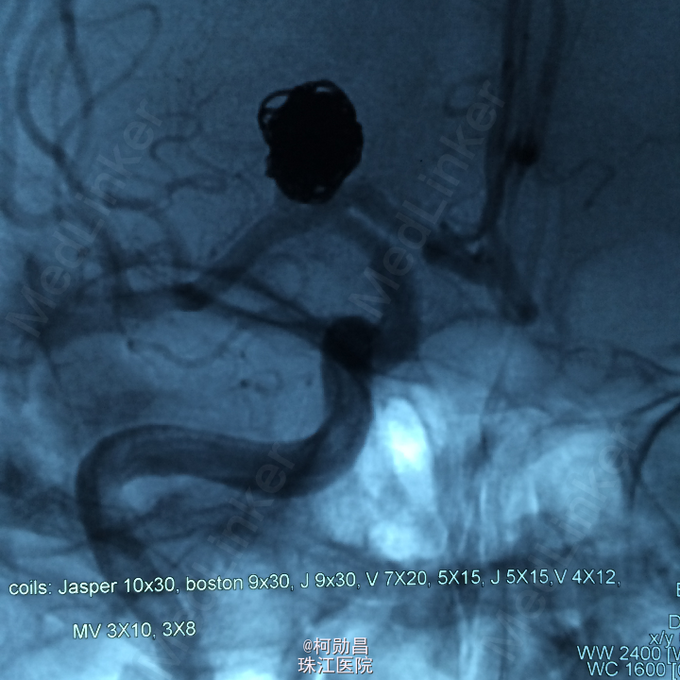

主诉:头痛半年余 病史:患者于半年无明显诱因出现头痛,为胀痛,严重时难以忍受,无头晕、呕吐、视物模糊、肢体抽搐等不适,遂至当地医院诊治,行CT检查提示:未见明显异常,行CTA检查提示:右侧大脑中动脉动脉瘤。患者为求进一步治疗而入我院。

查体:未见明显异常 辅助检查:头颅 CTA:前交通动脉动脉瘤

诊断:右侧大脑中动脉动脉瘤 处理:行DSA检查,重建血管3D,并行血管内栓塞治疗。

随访:患者症状缓解后出院 讨论: 血管内栓塞治疗为动脉瘤的首要治疗方案,但要注意栓塞后血管再通的问题。